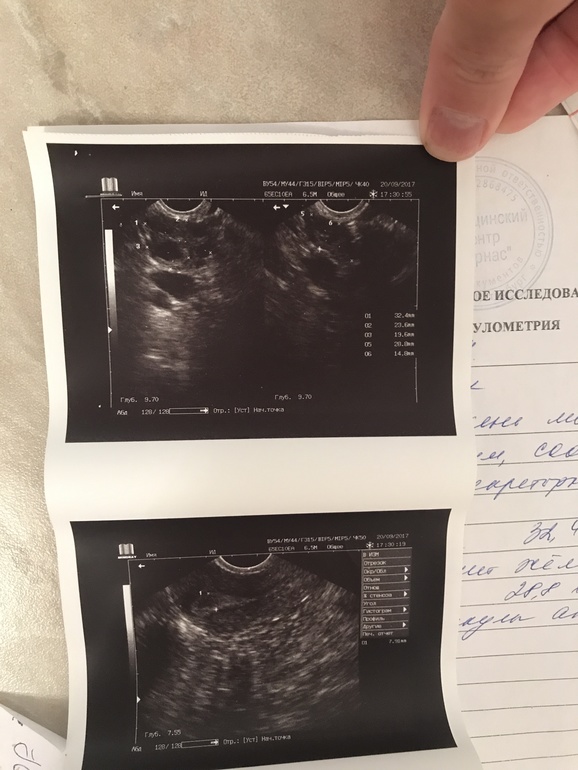

Сходила на Фолликулометрию

Сходила на УЗИ

Овуляция оказывается была , врач сказала тесты не информативны 🤗 Итак ЖТ 19,6мм в правом яичнике хоть болел левый , эндометрий 7,9 😕 Что скажете ? Это нормально ? Где то пол года назад делала Фолликулометрию на 23 дц жт было 17мм эндометрий 10мм и тогда врач давал надежду что возможно Б, так это на 23 день цикла , а сейчас 16 👆🏻 Блин че к чему ? В этом цикле начинаю пить дюф с 16 по 25 как советовал врач